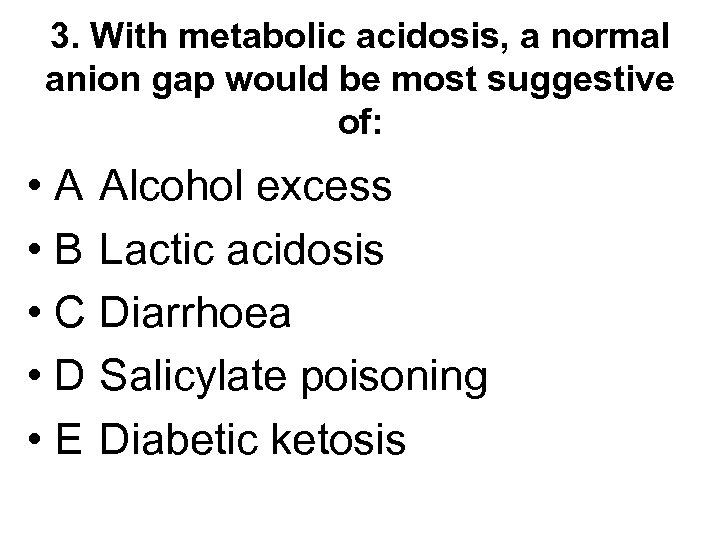

3. With metabolic acidosis, a normal anion gap would be most suggestive of: • A Alcohol excess • B Lactic acidosis • C Diarrhoea • D Salicylate poisoning • E Diabetic ketosis

3. With metabolic acidosis, a normal anion gap would be most suggestive of: • A Alcohol excess • B Lactic acidosis • C Diarrhoea • D Salicylate poisoning • E Diabetic ketosis

3. With metabolic acidosis, a normal anion gap would be most suggestive of: • A Alcohol excess • B Lactic acidosis • C Diarrhoea • D Salicylate poisoning • E Diabetic ketosis

3. With metabolic acidosis, a normal anion gap would be most suggestive of: • A Alcohol excess • B Lactic acidosis • C Diarrhoea • D Salicylate poisoning • E Diabetic ketosis

How do you know if acidosis is due to diarrhoea or to some other cause?

How do you know if acidosis is due to diarrhoea or to some other cause?

![Measure anion gap = [Na+ + K+] - [Cl- + HCO 3 -] Normal Measure anion gap = [Na+ + K+] - [Cl- + HCO 3 -] Normal](https://present5.com/presentation/69b3629f1f8c698a0ed008fa07ab29a0/image-19.jpg) Measure anion gap = [Na+ + K+] - [Cl- + HCO 3 -] Normal 12 -18 Diarrhoea RTA Urinary diversion Normal because when bicarb is lost kidneys retain chloride to maintain electroneutrality Raised >18 DKA Renal Failure Salicylate Methanol, ethylene glycol Raised due to presence of unmeasured anions

Measure anion gap = [Na+ + K+] - [Cl- + HCO 3 -] Normal 12 -18 Diarrhoea RTA Urinary diversion Normal because when bicarb is lost kidneys retain chloride to maintain electroneutrality Raised >18 DKA Renal Failure Salicylate Methanol, ethylene glycol Raised due to presence of unmeasured anions

Acidosis with raised chloride suggests diarrhoea, RTA or urinary diversion

Acidosis with raised chloride suggests diarrhoea, RTA or urinary diversion